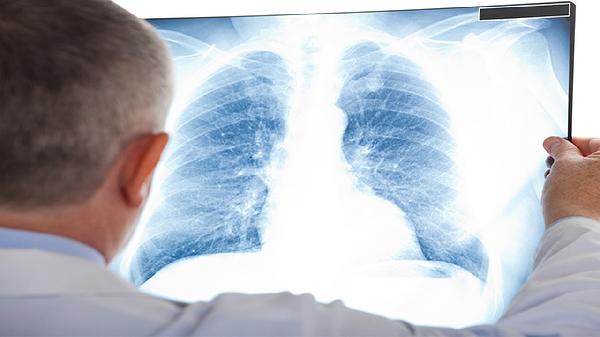

实性结节是转移肺癌最常见的表现形式,结节密度均匀且边界清晰,多见于结直肠癌、乳腺癌、骨肉瘤等血行转移的恶性肿瘤。这类结节在CT影像上呈现软组织密度,增强扫描时可能出现均匀强化,体积增长较快是其特征之一。部分实性结节可能伴有分叶状轮廓或毛刺征,需要与原发性肺癌进行鉴别诊断。

发现肺部结节应及时进行增强CT、PET-CT等检查评估特征,通过支气管镜或穿刺活检获取病理诊断。治疗需根据原发肿瘤类型制定个性化方案,可能涉及手术切除、放疗、靶向治疗或免疫治疗等多种手段。日常需避免吸烟及二手烟暴露,保持规律作息以维持免疫功能,出现持续咳嗽、胸痛等症状应立即复查。